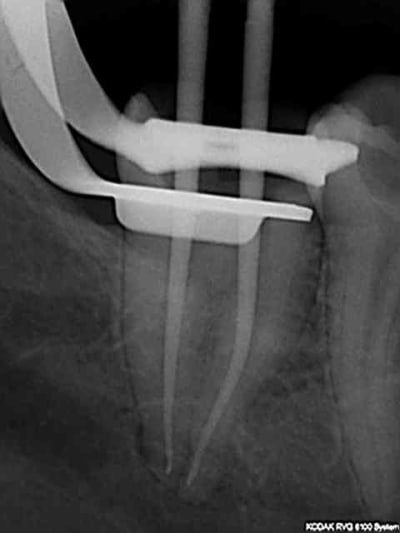

Pas de blouse, pas de radio pour vérifier la longueur.

> Pas de blouse, pas de radio pour vérifier la longueur.

90 mn 2 molar endo + extrac 38. Un peu lent du à la difficulté à anesthésier (30 mn). les crochets apicaux traités comme si ils n'existaient pas avec le r25.

les 6 canaux avec le même r25. Attention toutefois je m'y suis repris à plusieurs reprises pour envoyer le s1 à l'apex (alternance r25 s1) et une bonne ouverture des entrées au largo ainsi qu'une très large cavité d'accès. Je n'ai à ce jour jamais cassé de r25, mais jamais essayé avec les plots en plastique .)

cela n'était pas des petites racines lt 24-25 mm. Big up à la digue qui m'a apporté un très gros confort de travail et m'a fait gagner du temps. Il n'y a que les imbéciles qui ne changent pas d'avis.

Maintenant pour peaufiner l'action du sx avant le passage du s1 un petit coup de r25 pour progresser d'avantage n'est pas interdit (pas de fausse route avec pour l'instant)c'est ce que j'ai fait sur ces 2 molaires ou la radio préop laissait présager un peu de sport. )))

connais pas. Mais une de plus 30 mn, résultat reproductible à un train de sénateur, po pom, po pom.) Radio cone en place facultative mais bon des fois je coupe le bout du cone..